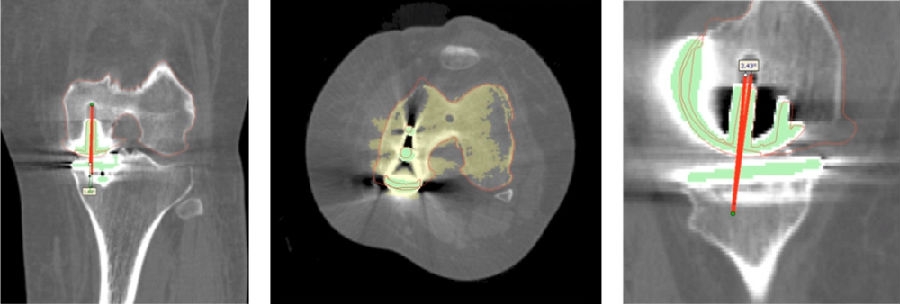

10、核查切骨与规划之间的吻合度

取下导板,取出骨块进行比对。注意对比厚度时要加上软骨的厚度如果吻合度有明显偏差,可以考虑徒手加截。

12、术后拍片

目前,笔者团队已经做了70多例,在早期探索过程中可能会出现一些问题,但是之后基本上都是比较好的,术后片子比较赏心悦目。

同时,笔者团队也在和导板公司进行合作,把用术后CT和术前CT进行匹配,来验证术前规划的偏离度有多少,包括胫骨后倾、冠状面内倾、轴面胫骨假体旋转、股骨在冠状面的角度、股骨在轴面上的旋转角度以及在矢状面上屈伸角度。

符合度验证